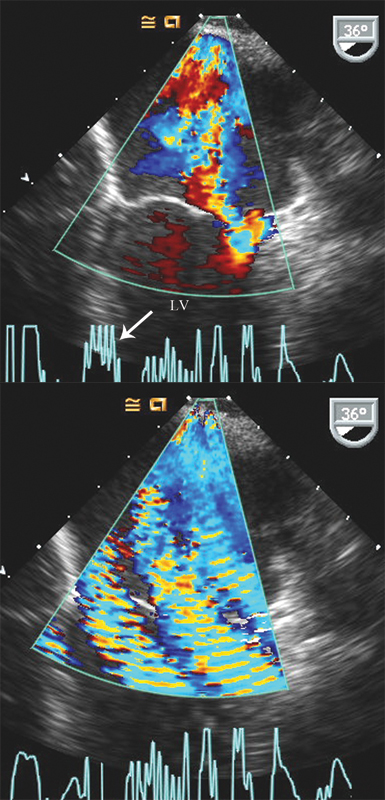

فحوصات تشخيصية لبعض امراض القلب والشرايين التاجية